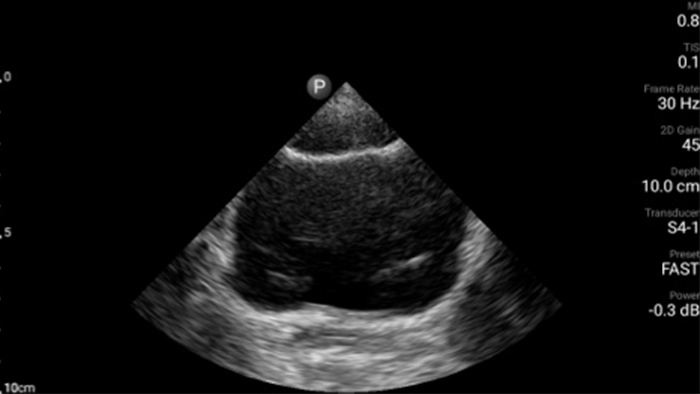

Casestudy

Een patiënt met dyspneu

Pre-klinische point-of-care-hartechografie: longembolie